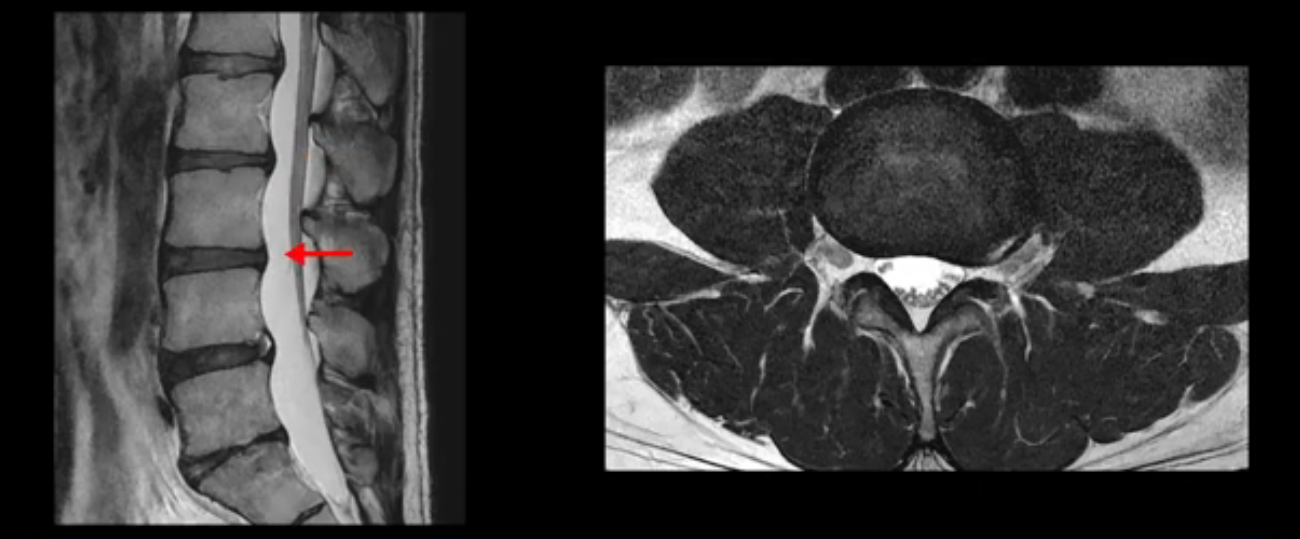

4번 5번은 가운데로 섬유륜이 찢어져서 디스크가 살짝 밀려나와 있지만 역시나 최근에 찢어지고 밀려나온 걸로 판단되지 않고 오래 전에 찢어진 흔적으로 보입니다.

왜 최근에 찢어진 급성이 아니고 오래된 거라고 하는지 이 부분도 뒤에 한꺼번에 설명 드리겠습니다.

5번 1번 역시 가운데로 디스크 조금 밀려 나와있지만 신경 공간 넓이는 아주 넓어서 신경 눌림 있을 거라고 예상이 안됩니다.

추간공도 보시다시피 왼쪽, 오른쪽 전부 다 매우 넓어서 신경이 눌릴만한 부분이 전혀 보이지 않습니다.